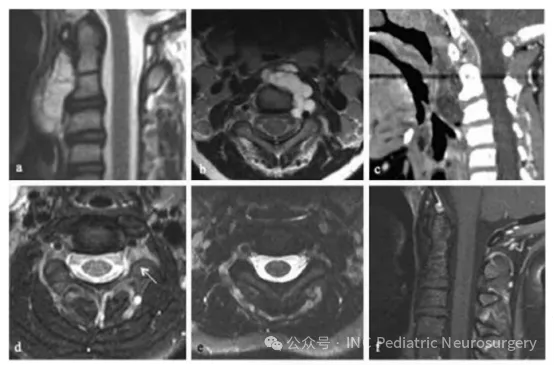

患者于2005年就诊,10岁。主诉为持续性颈部疼痛2年,伴有反复咽喉感染及吞咽困难。检查发现C1-C3脊索瘤,并导致上气道受压(图3)。患者首先接受经口活检,随后通过经口、经腭、经下颌联合入路实施肿瘤全切(gross total resection)。病理诊断为经典型脊索瘤。

术后影像显示左侧C2-C3神经孔内仍有残余病灶,经70Gy光子放疗后控制良好。患者对治疗耐受情况良好,术后10年随访无肿瘤复发、无神经功能缺损,保持无瘤状态。

图3. 患者4 C1-C3脊索瘤影像资料

(a)术前矢状位T1加权增强MRI;

(b)术前轴位T1加权增强MRI;

(c)术前矢状位CT;

(d)术后轴位T1加权增强MRI,可见C2-C3神经孔内小残余肿瘤(箭头);

(e)放疗后轴位T1加权增强MRI;

(f)放疗后矢状位T1加权增强MRI。